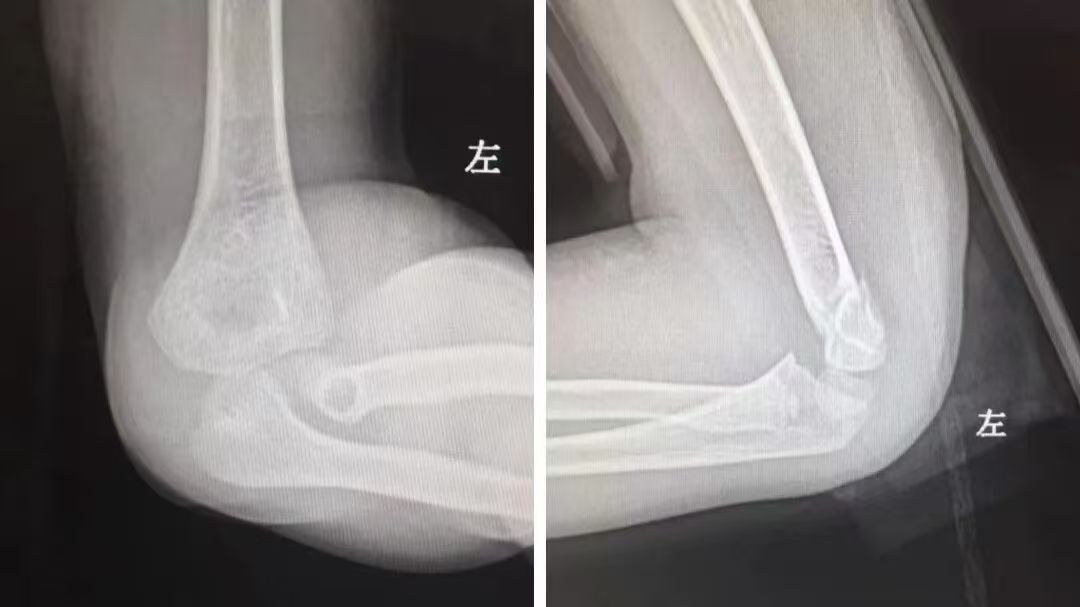

还有一例小儿骨折的实例,4岁的孩子在家玩耍时不慎摔倒,导致胳膊疼痛、不敢活动,哭闹不止,让家长心急如焚。“别着急,孩子不用手术,我们可以尝试手法复位来解决。” 张靖主任在仔细看片及检查后向家属解释道。

复位前影像资料

张主任一边轻声安抚孩子,一边精准施力,手上感觉到一声轻微的“咔嗒”声,复位成功!随后,为孩子患肢进行了小夹板外固定,复查X光片显示,骨折端对位良好。儿童骨膜较厚,血运丰富,骨折愈合迅速,所以,绝大多数儿童骨折只需要手法复位或夹板外固定就可以达到治疗目的。